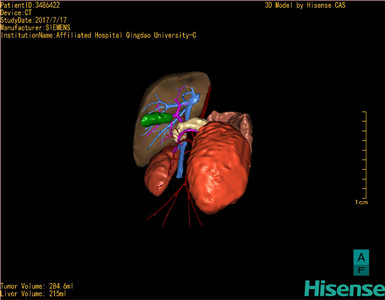

CT结果输入海信CAS系统后行3D重建及手术规划后,于2017-7-21全麻下行“左肾切除术”手术治疗:

术前三维重建及手术方案设计:

将0.625mm双源薄层CT资料的静脉期和动脉期Dicom格式文件导入海信CAS系统。

通过调节窗宽窗位调整CT序号,对肿瘤,肝实质,胆囊,下腔静脉,肿瘤,肝动脉、门静脉及肝静脉等进行三维重建;系统自动计算肿瘤体积和肝脏体积。

模拟手术操作,自动计算切除肿瘤体积。肝脏体积为215ml,肾脏肿瘤大小为284.6ml通过术前模拟手术,精准判断手术可行性。

术前三维重建:

重建图片